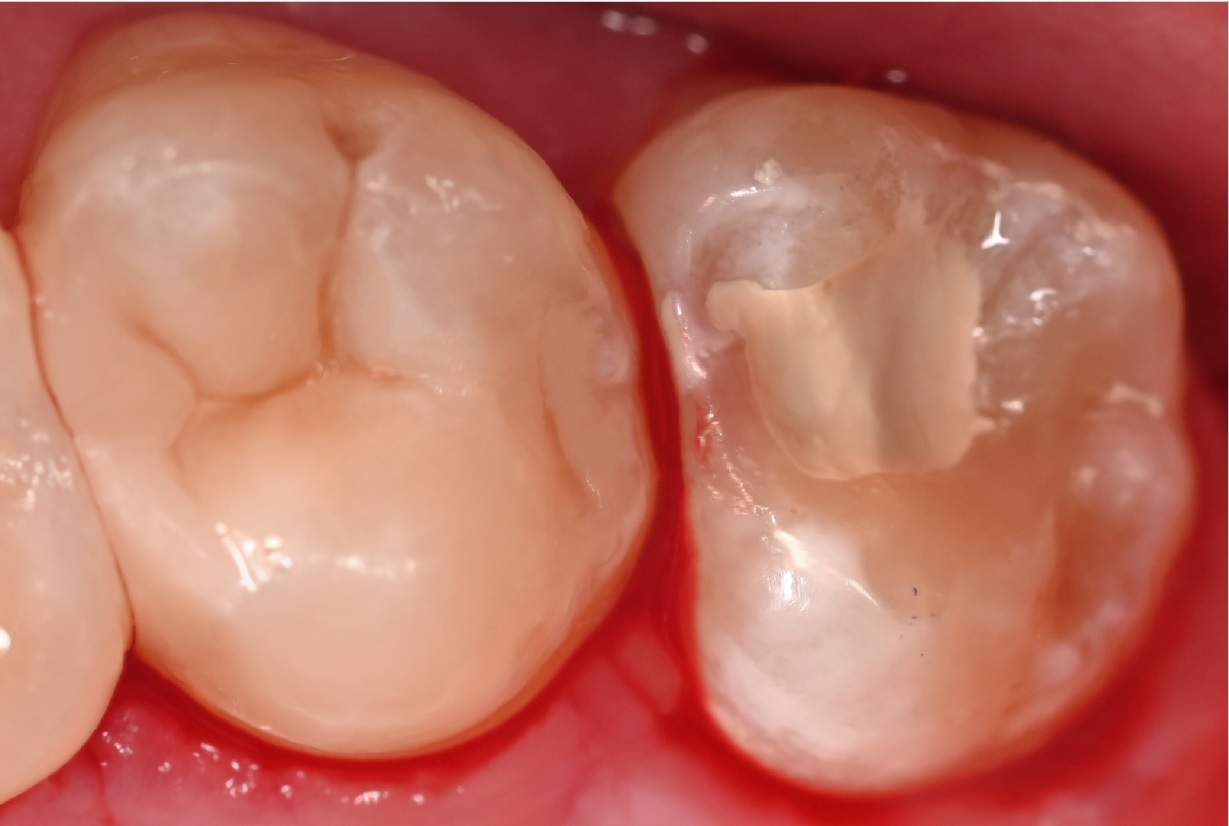

Εικ. 3: Μετά την αφαίρεση της προηγούμενης αποκατάστασης σύνθετης ρητίνης και τον καθαρισμό της τερηδονισμένης αλλοίωσης στον τρίτο γομφίο, παρατηρήθηκε μια βαθιά κοιλότητα κοντά στον πολφό. Και στις δύο περιπτώσεις, αποφασίστηκε η εφαρμογή του Biodentine XP χρησιμοποιώντας μια τεχνική biobulk-fill για την έμμεση κάλυψη του πολφού, με σκοπό την αποκατάστασης της οδοντίνης, την παροχή ενός προστατευτικού φραγμού και τη διατήρηση της ζωτικότητας του δοντιού.

Εικ. 4: Αφού οι κοιλότητες είχαν προετοιμαστεί και καθαριστεί, το Biodentine XP εφαρμόστηκε απευθείας στην βαθύτερη περιοχή της κοιλότητας.

Εικ. 5: Μια κοιλότητα Ομάδος Ι είναι πιο επιθετική στην αφαίρεση όλου του κατεστραμμένου ιστού σε σύγκριση με μια κοιλότητα Ομάδος II και μπορεί να προκαλέσει μεγαλύτερη ευαισθησία. Για να αξιολογηθεί η διατήρηση της ζωτικότητας του πολφού στον τρίτο γομφίο, ο οποίος ήταν ο πιο επηρεασμένος, εφαρμόστηκε το Biodentine XP χρησιμοποιώντας μια τεχνική biobulk-fill, γεμίζοντας πλήρως την κοιλότητα μέχρι την μασητική επιφάνεια ως προσωρινή αποκατάσταση. Αυτή η προσέγγιση επιτρέπει την αναβολή της οριστικής αποκατάστασης, διασφαλίζοντας παράλληλα την σωστή έμφραξη της κοιλότητας για την αποφυγή επιμόλυνσης. Επιπλέον, επιτρέπει την αξιολόγηση της διατήρησης της ζωτικότητας του πολφού και καθορίζει αν απαιτείται ενδοδοντική θεραπεία αν τελικά δεν διατηρηθεί η ζωτικότητα.

Αντίθετα, για τον δεύτερο γομφίο, η ολοκλήρωση της αποκατάστασης Ομάδος II ήταν προτεραιότητα. Έτσι, τοποθετήθηκε το Biodentine XP, αφέθηκε να πήξει και στη συνέχεια καλύφθηκε με σύνθετη ρητίνη για να επιτευχθεί η τελική αποκατάσταση.